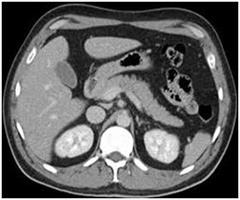

Your doctor has ordered a CT (Computed Tomography) of your abdomen. CT is an advanced form of X-rays that uses a narrow X-ray beam and advanced computer software to create detailed cross-sectional images of the body organs.

CT scans of the abdomenCT scans of the abdomen